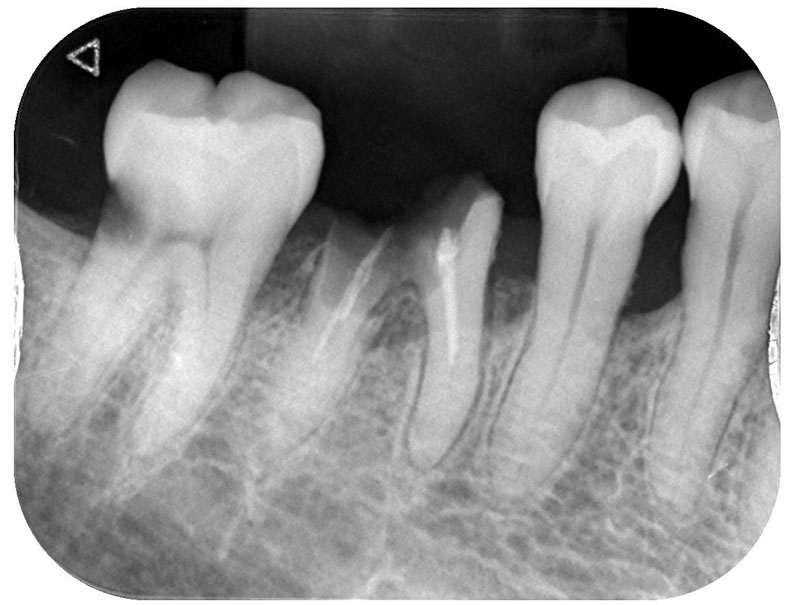

レントゲン写真およびCT画像なのですが、右上6が残歯状態であり歯根破折を起こしている状態でした。しかし歯槽骨から上顎洞底までの距離は十分に認められます。この歯槽骨から上顎洞までの距離がないとソケットリフトなどのオプションの処置が必要になってくるのですが、今回の症例では大掛かりな処置の必要はなく症例の難易度としては比較的イージーな方でした。上顎洞などに関して知りたい方はこちらのページを参照にしていただければと思います。

インプラント埋入手術

インプラントの埋入に関しては1回法で行いました。抜歯した部位の骨はしっかりと治癒していました。インプラント埋入後はヒーリングキャップと言ってインプラント周囲の歯茎の形態を整えるためのキャップを装着しました。手術時は特に大きな問題はなく無事に手術が終了しました。